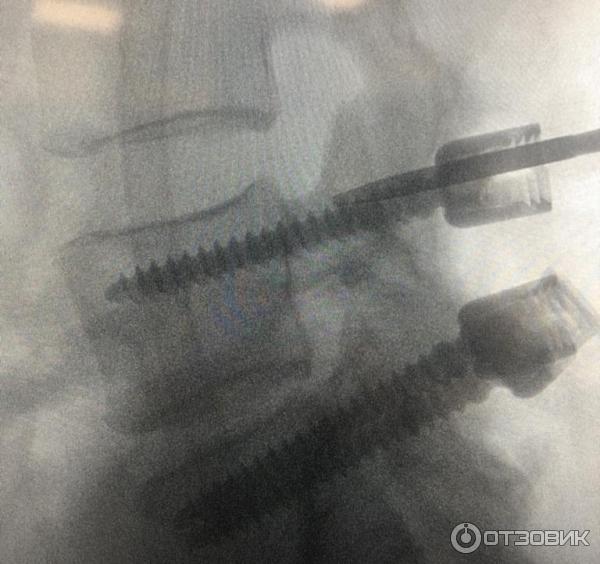

Нейроуридин - капсулы с хорошим обезболивающим эффектом! Принимала по рекомендации врача при защемлении нерва . Были боли просто адские, невозможно было повернуть шею в другую сторону .